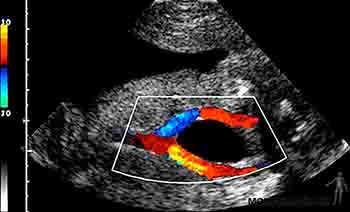

Durante el cuarto mes el feto crece rápidamente, aun cuando el peso se incrementa lentamente, de manera tal que a mediados del período gestacional tiene la mitad de la talla de un recién nacido, pero pesa menos de 500 gramos. Al cuarto mes la piel del feto está cubierta por un vello fino, el lanugo, y son visibles las cejas y el cabello. Ecográficamente en esta etapa es posible identificar el cordón umbilical y visualizar en él la vena y las arterias umbilicales, siguiendo su trayecto en el abdomen del feto (Figuras 2-20a y b).